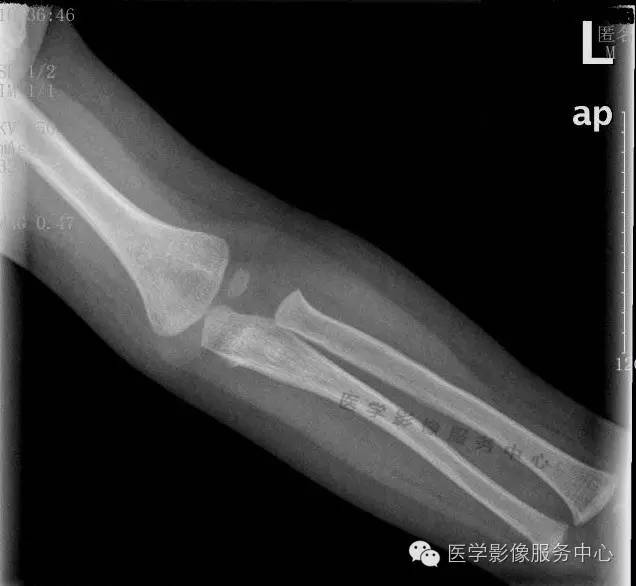

影像图片

你能发现问题吗?

相信大家都看到了吧,肘关节没问题,肱骨骨折。急诊基本都是小医生在做,现在工作量又大,平片最忌一下就盯住阳性的或临床医生申请的,但是现在的临床医生有几个认真望触叩听的,千万别太相信他们!出了事尽量往辅助科室推是他们临床的潜规则,所以急诊一定要认真,片子上的全都要看一下,我习惯先看不重要的然后才看重要的,真的遇到好几次这种情况,拍肋骨正斜位结果锁骨或肩胛骨骨折的都不知道多少个了,我科技术员习惯站着拍,可倒好!连拍肩关节气胸的或肺挫伤的都有!还有一次拍骨盆结果腰椎骨折,拍腰椎结果带到的一根肋骨骨折,最夸张的一次我科纠纷,外伤颈椎正侧位,结果有次第1肋骨骨折漏掉了!没办法临床弱辅助科室想不漏诊都难!

本例我科漏诊原因我认为

1是被误导,但是小儿外伤定位较难,技术员拍片连光圈、球管都懒得调的,致使明明拍一个部位结果会显示很多其他的;

2是只有侧位看见骨折线,但是骨折线又紧邻家长扶着的手边,很容易以为是外边的伪影,说实在的要不是那个小骨片刚开始我也以为是伪影呢。